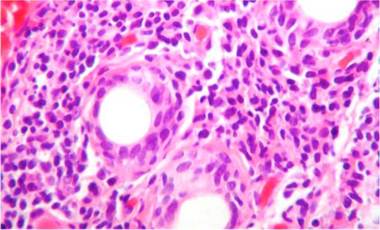

Ante la complejidad del caso y sin una etiología clara del proceso pulmonar, considerando que el TEP no era la única causa de la hipertensión pulmonar, se decidió en una junta la realización de biopsia de pulmón. Esta patología mostró como resultado la presencia de una neumonía intersticial no específica subtipo predominante celular (figs. 2 y 3), por lo que se inició manejo con prednisolona a dosis de 1 mg/kg/día, por 10 días. Con el fin de determinar causas secundarias, se ordenaron pruebas autoinmunes, las cuales mostraron positividad para anticuerpos antinucleares con una dilución de 1:640, patrón moteado fino. La medición de autoanticuerpos específicos mostró AntiSSA >200U/ml (VN: <15U/ml), y AntiSSB >200 (VN: <15U/ml). El resto de perfiles autoinmunes, incluyendo anticuerpos anti-Sm 2,6U/ml (VN: <15U/ml), AntiRNP 0,8U/ml (VN: <15U/ml), anticardiolipinas IgG 4,3GPL-U/ml (VN: < 10 GPL-U/ml) e IgM0,5 MPL-U/ml (VN: <7MPL-U/ml), fueron todos negativos.

Figura 2 Biopsia de una cuña pulmonar. A) Tinción de H & E. B) Pentacrómico de Russell-Movat. Se observa un patrón histológico de neumonía intersticial inespecífica de predominio subtipo celular.